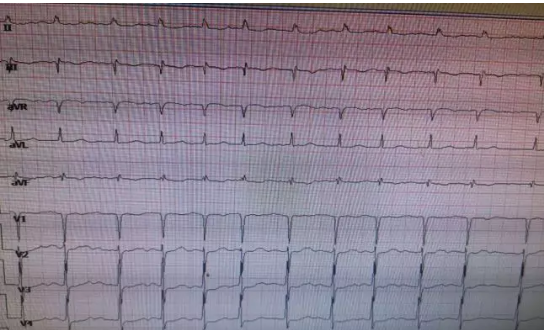

(三)心電圖:室性心動過速心電圖顯示寬大的QRS波形,時間一般超過0.12秒。室上性心動過速心電圖顯示較窄的QRS波形,時間一般不超過0.12秒。

微信截圖_20210615082207.png

圖1、陣發性室上性心動過速心電圖